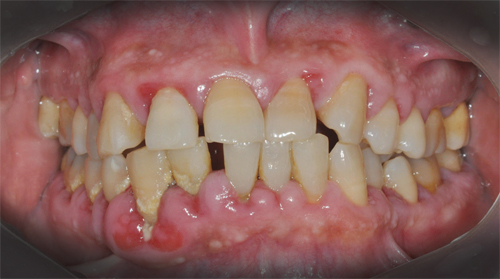

우리의 입속에는 600~700종에 달하는 미생물이 살고 있는데요.

사람마다 서식하는 박테리아 종류와 구성이 다 다릅니다. 중요한 것은 그 세균들 중에는 췌장암을 일으키는 세균이 있습니다.

미국 국립 암연구소와 미국 암 학회지가 10년동안 추적해오면서 14만명을 조사한 자료에 따르면 입 속 치주염을 일으키는 세균이 췌장암과 연관성이 있다고 발표했습니다.

또한 과학 전문매체 유레카 얼러트에 따르면 췌장암 환자들이 치주 질환에 취약하고 이가 잘 빠지는 구강 건강과 췌장암의 관계를 시사하는 연구는 기존에도 있었다고 합니다.

치주염 진지발리스 박테리아가 입 속에 있다면 췌장암 발생 위험율을 59% 높인다고 합니다.

잇몸에 염증이나 피가 나는 사람은 염증에 세균이 침투해 혈액을 타고 이동하고 췌장에 도달하게 되면 췌장암으로 변질됩니다.

입 속 세균인 진지발리스 혈중 항체가 높다면 췌장암 위험이 2배가 증가하며 치주질환을 앓았던 경험이 있는 사람은 췌장암 위험이 64% 증가한다고 합니다.

그래서 입속 치주 질환은 단순 구강 문제가 아니며 치주질환의 직접적 원인이 구강내 세균이며 그 세균으로 인해 췌장암 위험이 높아집니다.

그렇기 때문에 입속을 어떻게 관리하느냐가 췌장암 예방에 가장 중요한 방법이 됩니다. 양치할 때 피가 자주 나거나 입속에 염증이 있다면 방치하지 말고 얼른 치료를 해야 합니다.

늘 입속에 염증이 생기지 않도록 치아와 잇몸 관리에 신경을 써야 합니다.

입 속세균이 혈관을 타고 이동하면서 몸속 질환을 유발하고 치매와 심장질환까지 발생시킬 수 있기 때문에 입 속 염증 세균이 무섭습니다.